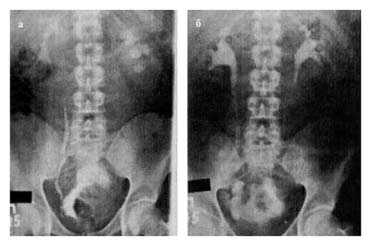

15.10 проведена операция: радикальная цистэктомия, резекция уретры с формированием континентного гетеротопического резервуара по описанной выше методике, гастростомия. Гистологическое заключение от 21.10: высокодифференцированный переходно-клеточный рак, врастающий в мышечный слой стенки мочевого пузыря. Послеоперационный период протекал без осложнений. Гастростома удалена на 10-е сутки, мочеточниковые катетеры на — 13-й и 14-й дни. На 21-й день выполнены резервуарограмма и внутривенная урография — выхода контрастного вещества за пределы мочевых путей нет; на урограмме — выраженная положительная динамика со стороны верхних мочевых путей (рис. 10, а,б). Катетер из резервуара удален. При катетеризации резервуара катетер свободно проходит через клапан, промежуток между катетеризациями — 3 ч. Больной наблюдается 28 мес: метастазов и рецидивов опухоли не выявлено, удерживающая функция резервуара и качество жизни удовлетворительные.

Рис.10. Экскреторная урограмма, выполненная у больного Д., 32 года, до (а) и через 3 недели после (б) операции